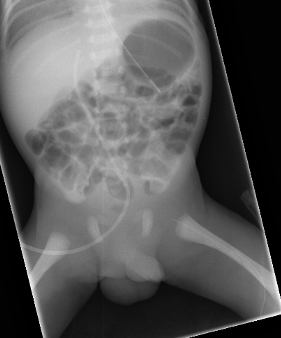

PICC line which has failed to advance beyond the hip joint

Inadvertent insertion into the lumbar vein

This complication is rare and predominantly affects PICC lines inserted into the left leg. Possible warning signs that the line has entered the lumbar vein may include some of the following:

- Failure to advance the line as far as anticipated

- The PICC line does not cross the midline to lie to the right of the spine on x-ray

- The PICC line that has an unexpected kink or deviation to its path on x-ray.

- A lateral X-ray may demonstrate deviation of the line posteriorly

See illustrative x-rays below.

If there are any concerns that this complication has occurred, a lateral x-ray may show the line deviating posteriorly. If possible, seek advice from radiology about further imaging.

Such lines must not be used and the catheter should be removed. These lumbar veins are small, and extravasation of the infusate into the spinal canal may readily occur. This may result in permanent neurological injury and seizures.

These two x-rays show PICC lines that have entered the left lumbar vein. In both cases the line has not crossed the midline and lie to the left of the spine. Both X-rays show a kink in the route (arrow) although it is important to note that these kinks were not apparent on the initial x-rays and this feature cannot be relied upon |